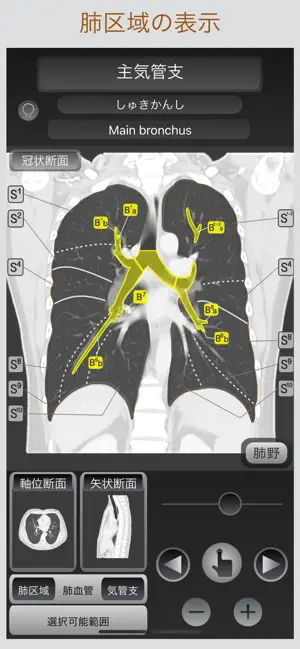

このアプリでは、画像に触れるだけでその解剖名称を表示し、すぐに目的とする箇所を調べられるだけでなく、軸位断面・冠状断面・矢状断面の切り替え表示が可能であり、選択部位の位置関係を瞬時に把握することが出来ます。

■断面の切り替え表示

サブ画面を選択する事で、目的の断面と切り替え表示が可能です。

■肺区域・肺血管・気管支の表示

肺区域・肺血管・気管支をCT画像上に表示出来ます。